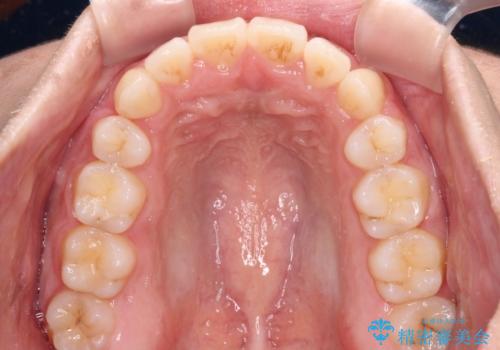

- 前歯のデコボコと口元の突出感を気にして来院された患者様です。

上下左右第一小臼歯4本を抜歯し、ワイヤー装置にて口元を引っ込めるよう矯正治療を行うこととしました。

非常にスムーズに歯列移動が行われ、当初は2-2.5年を予想していましたが、僅か1年4ヶ月で治療を終えることができました。